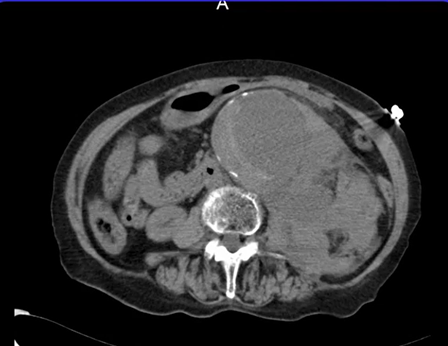

80歳女性。腰背部痛を訴え、来院時にはショック状態で意識レベルが低下していた。

補液にてバイタルを安定させながら単純CT施行。

腹部大動脈の拡張と、周囲に紅斑に広がる血腫あり。

診断:腹部大動脈破裂

状態が許せば造影CTにてより詳細を確認。